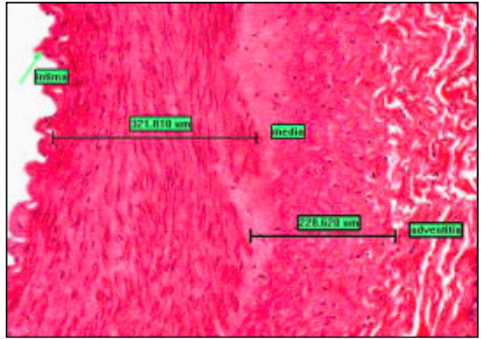

ARTERY - LEFT, VEIN - RIGHT

- 3 layers

- intima (innermost) - endothelial cells on loose connective tissue w/ occasional myo-intimal cells (contractile potential)

- media (middle) - thicker in arteries than in veins - smooth muscle, elastic, collagen

- adventitia (outermost) - dense collagen and elastic

MUSCULAR ARTERY

- well defined medial layer (smooth muscle in concentric rings)

- medial layer interspersed with elastic

- media-intima divide = wavy internal elastic lamina (condensed perforated elastic)

- adventitia-media divie = external elastic lamina only in large muscular